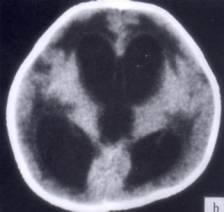

问题 病历摘要:??患者女性,10岁。结核性脑膜炎愈后8月,头痛伴恶心呕吐1周,并渐加重。体检:神清,精神差,反应迟钝,双眼底视神经乳头水肿,双眼外展差,余未见明显异常。 下列关于脑积水的叙述哪些是正确的?

选项 A.按阻塞部位分:梗阻性脑积水和交通性脑积水 B.按脑脊液蓄积部位分:内部性脑积水和外部性脑积水 C.正常颅压脑积水是指脑室扩大,但脑室内压力正常 D.正常颅压脑积水主要症状是步态不稳、记忆力障碍及尿失禁 E.儿童脑积水多为先天性和炎症性病变所致 F.成人脑积水多为颅内肿瘤、蛛网膜下腔出血和外伤所致 G.婴儿脑积水典型症状有Macewen征、日落征等